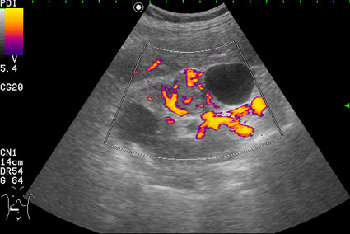

- Сканирование в режиме энергетического доплера.

Вас не смущает наличие внутреннего кровотока в одной из "кист"?

Но Вы правы в том, что могут быть трудности в дифференциальном диагнозе между AML и RCC малых размеров (в 20-30 % случаев могут быть эхогенными). Однако при УЗИ для RCC характерен гипоэхогенный ободок, внутриопухолевые включения, низкорезистивный внутриопухолевый кровоток.

Гипоэхогенный ободок, если очень постараться, можно найти на фото 1. Внутриопухолевые включения отсутствуют в обоих случаях. Могу согласиться только на низкорезистивный внутриопухолевый кровоток (в AML он действительно отсутствовал, хотя этого я нигде не отмечал).